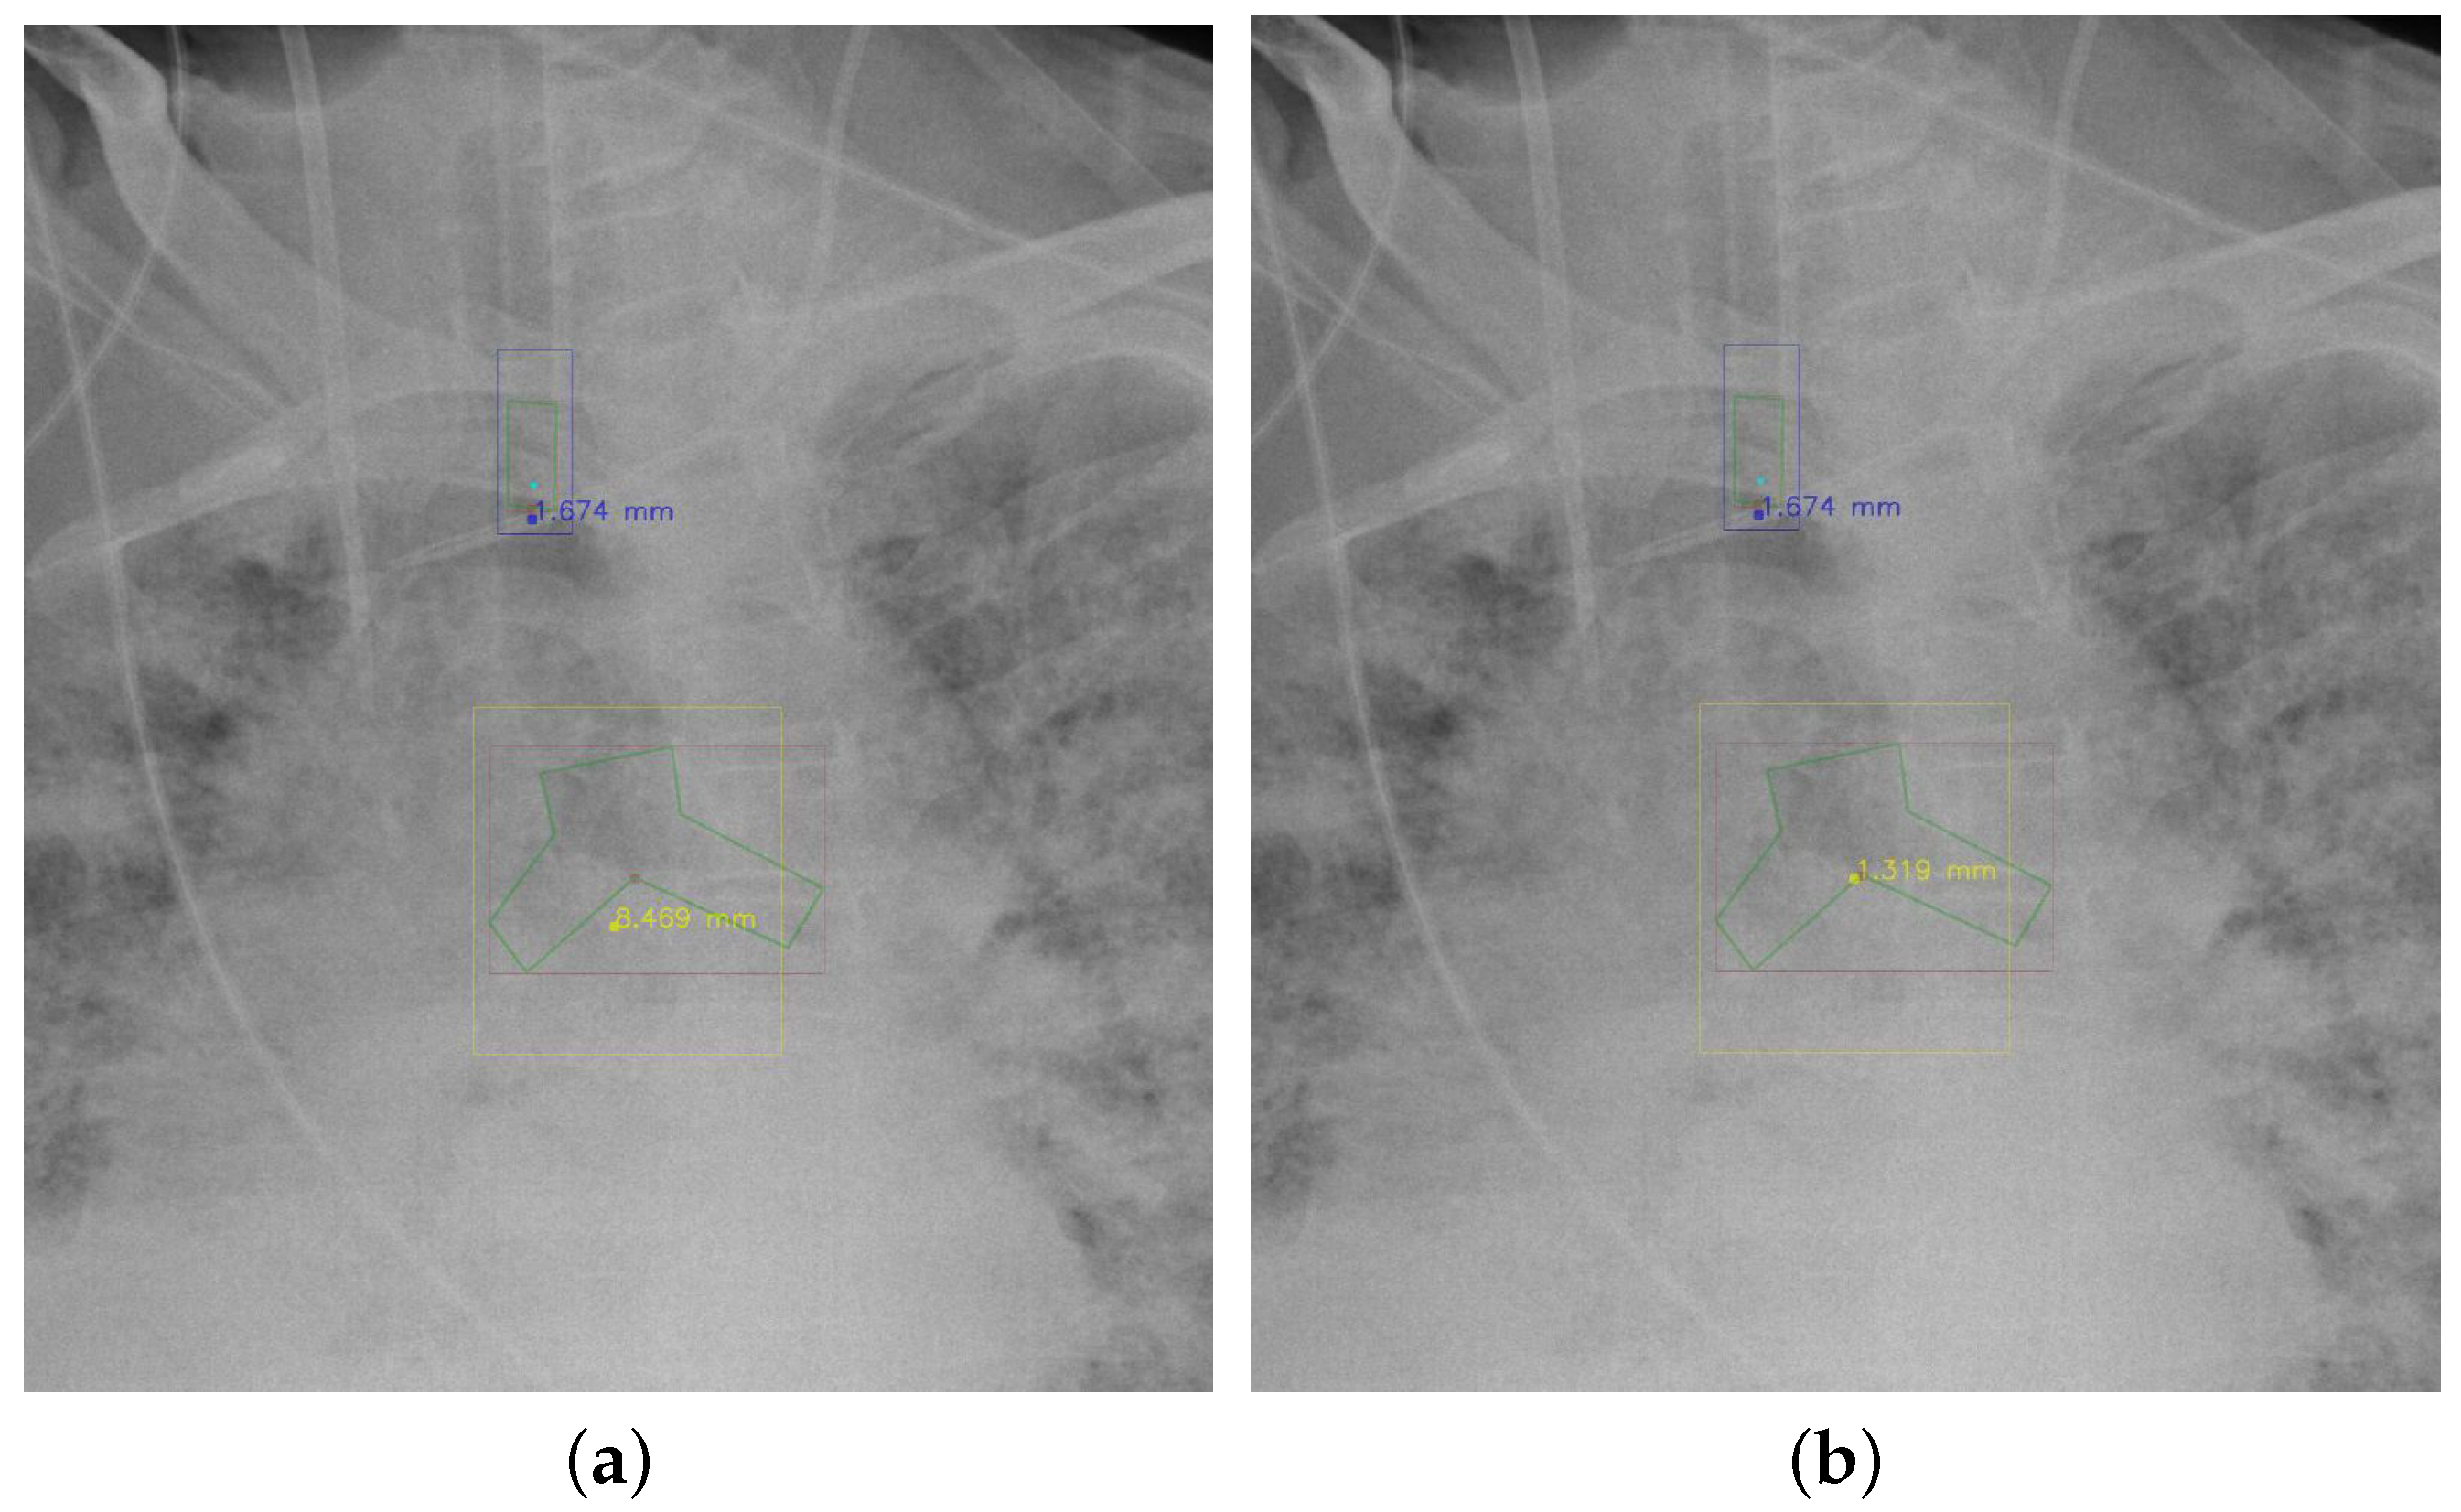

4.5.7. The Post-Process Algorithm

Figure 7 and Figure 8 demonstrate the effect of post-processing. The red bboxes and points in these figures are the GT ETT/bifurcation bboxes and the position of GT ETT tip/Carina, respectively. The green polygon is the GT mask of the ETT and the bifurcation. The blue bbox and point are the predicted ETT bbox and ETT tip, respectively. The yellow bbox and point are the predicted bifurcation and Carina, respectively. Specifically, without the post-process, the model might leave more than one predicted ETT tip/Carina, such as where the red arrow points in Figure 7a. However, with the post-process, the extra points would be removed as shown in Figure 7b. Besides, with the refinement process in the post-process, the feature point of ETT tip/Carina could be further refined as shown in Figure 8. Concretely, the object error of Carina was corrected from 8.469 mm to 1.319 mm.

Figure 8. Refining the feature point of ETT tip/Cairna by the bbox of ETT/Bifurcation. (a) Without post-process. (b) With post-process.

Diagnostics 12 01913 g008